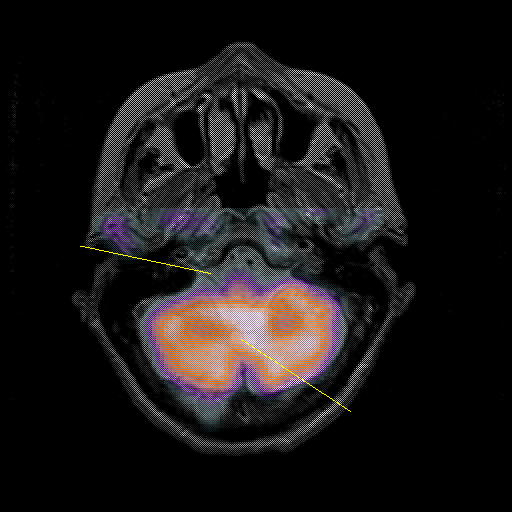

overlay : Slice 11

Slice 11

MRCBFCBF with